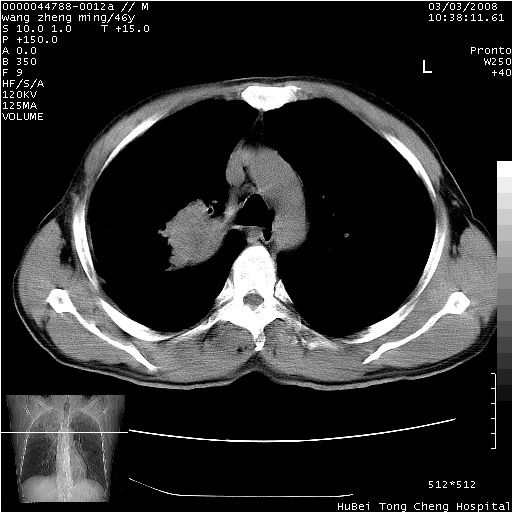

以下是引用卜一在2008-3-22 1:37:00的发言:[br]右肺实质性肿块,边缘不整,明显见毛刺征 分叶征及胸膜凹陷征,右上叶支气管明显变窄,远端散在的片状 斑片状实变影。另:左肺门较大肿块,支气管受累 变窄,远侧见阻塞性肺炎。纵隔内见肿大淋巴结。多考虑:右肺周围性肺癌伴左肺门 纵隔淋巴结转移!